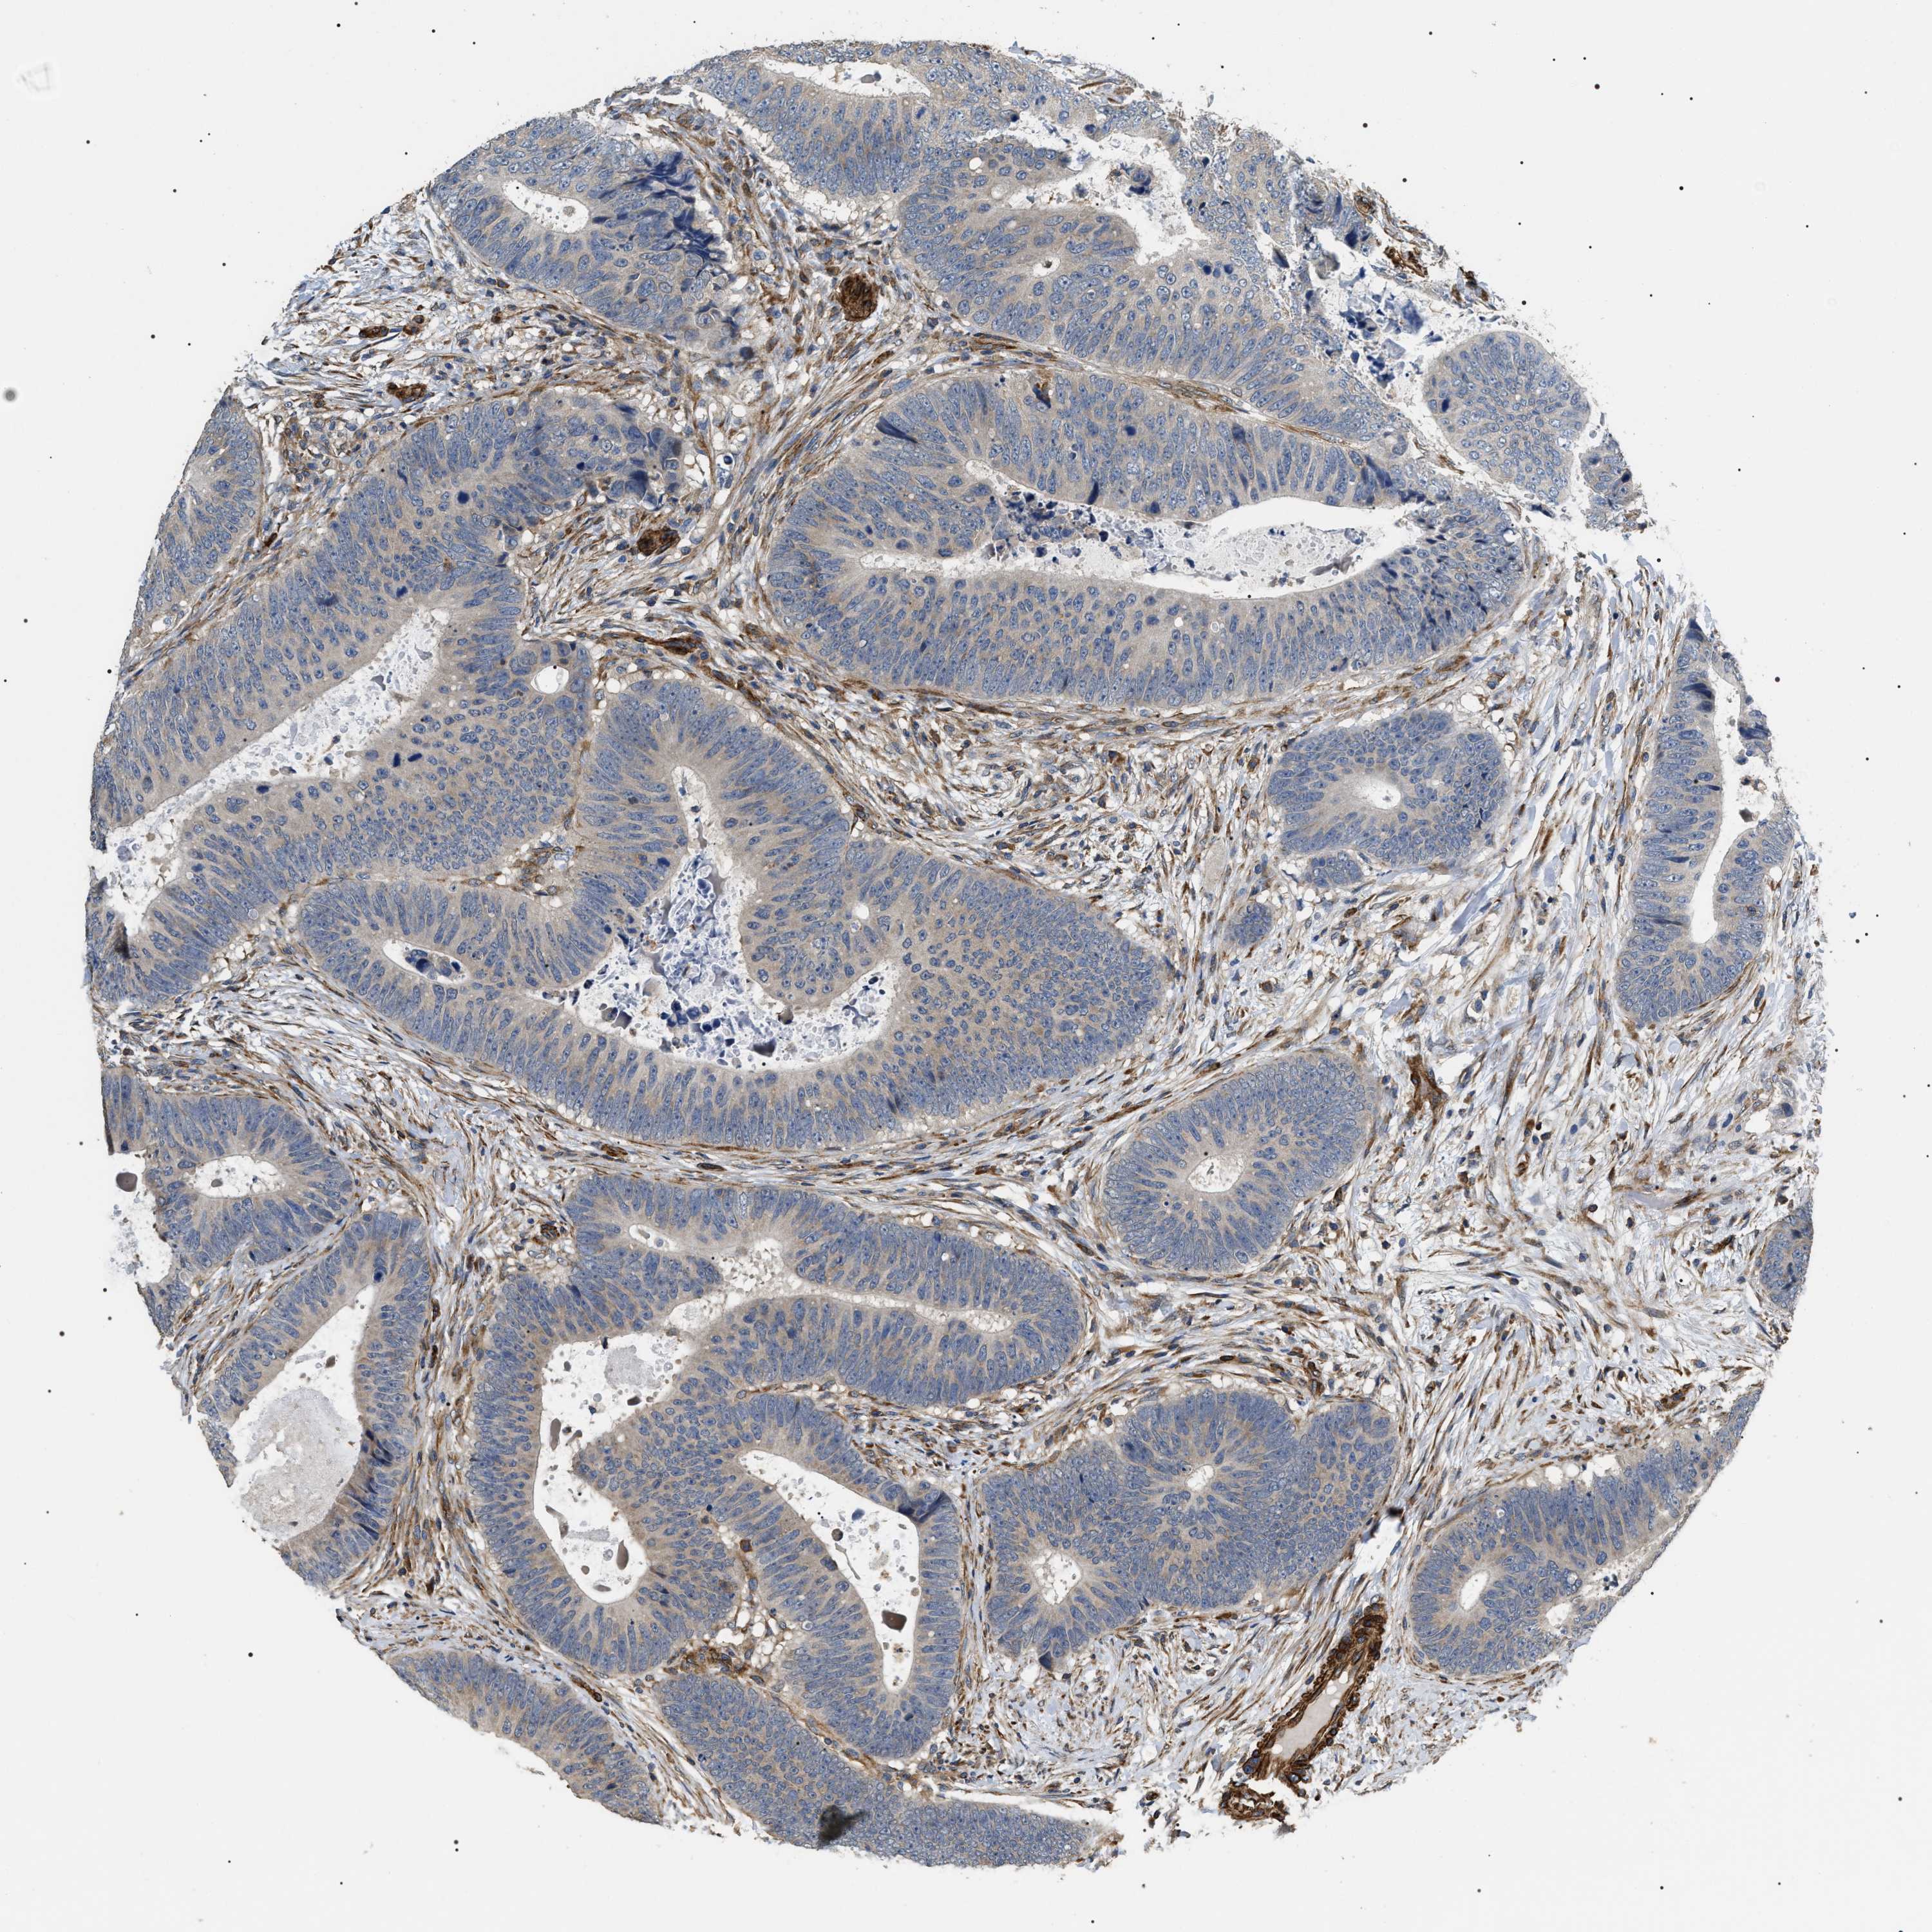

CANCER COLORECTAL CANCER Show tissue menu

Colorectal cancer

Human cancer

Colon adenocarcinoma